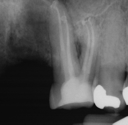

Conventional Endodontic Treatment with Post and Core Coronal Restoration

Conventional Endodontic Treatment/Retreatment with Prefabricated Bonded Post and Core